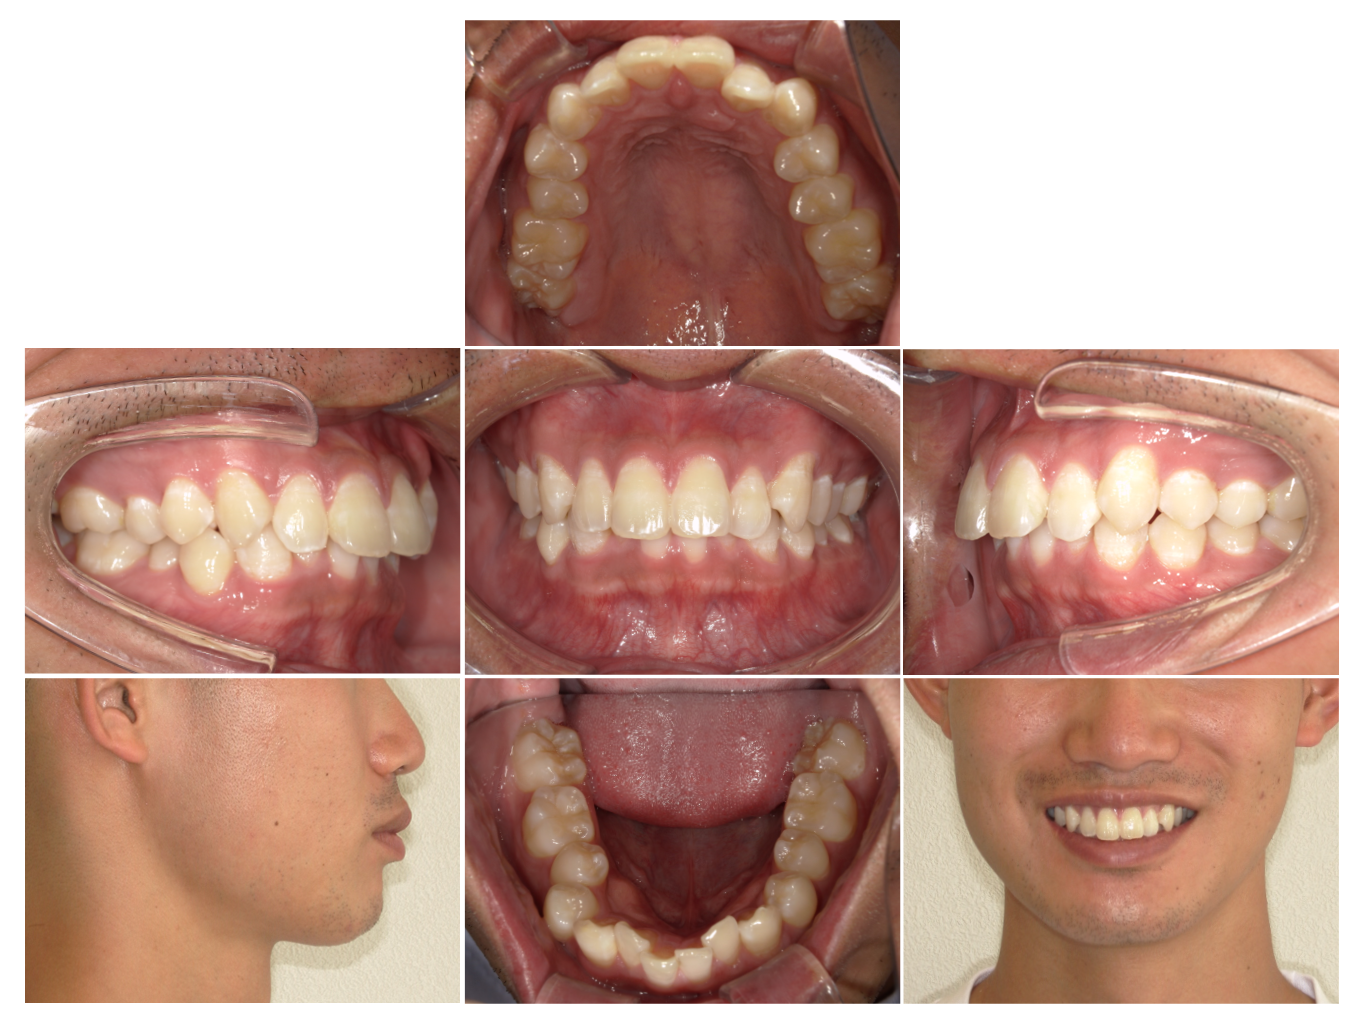

症例7

| 来院時の主訴 | 全体的なガタガタ |

| 医院での対応や適用装置 | マウスピース矯正装置を使用して主訴である |

| 通院期間 | 8ヶ月 |

| 通院回数 | 6回 |

| 治療費用総額 | 726,000円(税込) |

| リスクと副作用 | 矯正治療による歯の移動に伴う痛み、歯根吸収、虫歯 |